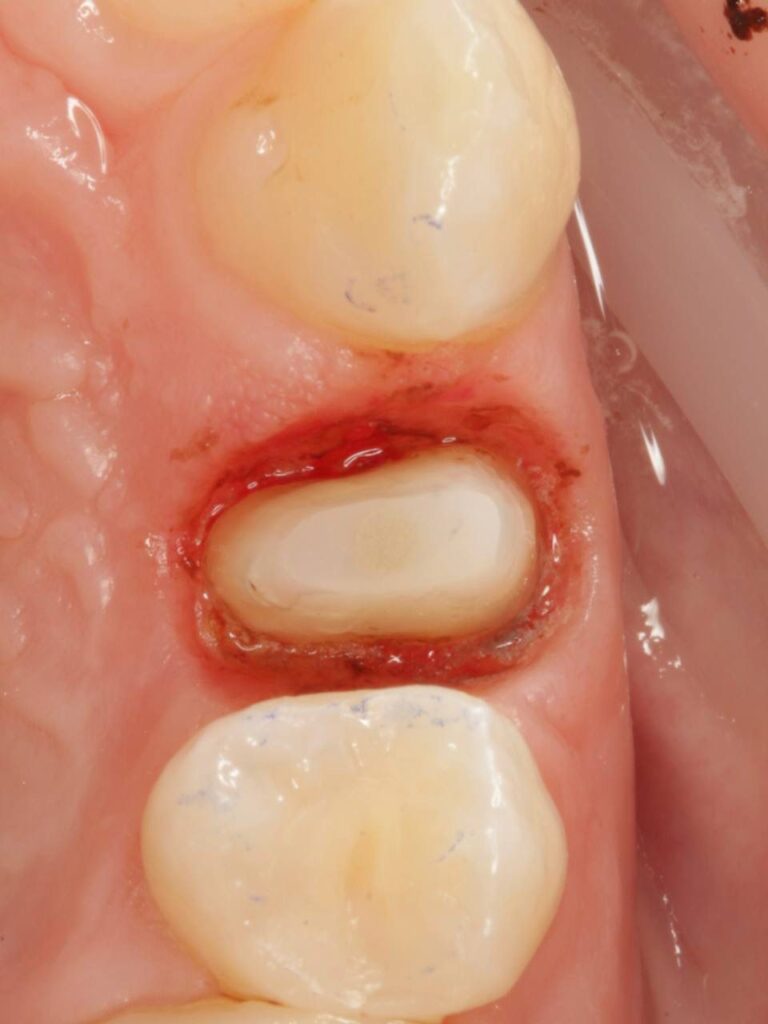

Специализация: терапия(эндодонтия), ортопедия, имплантология.